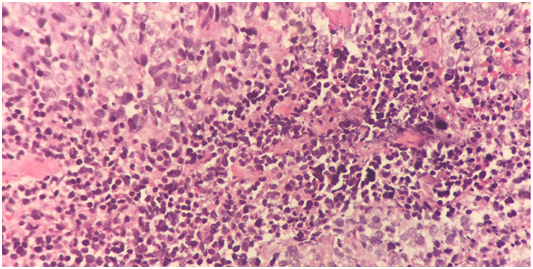

7 years old boy presented with history of left neck mass, headache and weight loss for 1-month duration, with limited range of motion of the neck and increasing pain in that region for 5 days before he was referred to our hospital. Physical examination revealed left upper cervical swelling measuring 5x6 cm in diameter, firm in consistency and attached to the underlying structures, no neurological deficit of signs of respiratory compromise was observed. His initial laboratory results are shown in Table 1. Cervical lymph node biopsy revealed reactive lymph nodes, negative for granulomata and negative for malignancy. Magnetic resonance imaging (MRI) of the neck (Figure 1) showed evidence of perivertebral/retropharynegal large multilobulated soft tissue mass measuring about 7.9x8.7x6.9 cm in transverse, craniocaudal and at the posterior dimensions respectively, extending in the nasopharyngeal region, and extending opposite to the skull base, clivus and upper cervical vertebra body posteriorly with the extension through the neural foramina of C1 and C2 vertebrae and causing bony erosions, extending into the spinal canal, however the signal intensity of the spinal cord was preserved, with narrowing of the right vertebral artery and questionable tumour involvement at the level of C1. Superior extension of the mass is seen obstructing the nasopharynx, anteriorly the mass is seen compressing the nasopharynx and exerting mass effect on the oropharynx with no patent airway seen around endotracheal tube. Infiltration of the hard palate and palatine tonsils were seen, laterally the mass seen compressing the carotid vessels bilaterally with suspicion of marked compression and occlusion of the left jugular vein, however the carotid arteries were patent. The patient underwent incisional biopsy of the retropharyngeal mass and bilateral bone marrow aspiration & biopsy. During surgery patient was electively intubated and due to difficulty in extubating and critical obstructed airway a tracheostomy tube was inserted to ensure patent airway. Histopathological examination of the retropharyngeal mass showed small blue cells with scant cytoplasm (Figure 2). Immunohistochemical studies showed that tumor is positive for CD99 and Vimentin, negative for Myogenin, TTF-1, Pankeratin, Desmin, Chromogranin,CD45, Synaptophysin, SMA, MSA ,CK7,EMA,CD56, CD34, and PAX5. Fluorescence in situ hybridization (FISH) study showed fusion of the ESWR1/FLI1 genes associated with the translocation t(11;22)(q24.3;q12.2) Thus radiological, histological and immunohistochemical finding were confirmatory of Ewing sarcoma of the retropharyngeal space. Bone scintigraphy showed no evidence of bone metastasis. As incidental finding on CT abdomen revealed a single hypertrophied right kidney with mild hydronephrosis. Renogram was done and showed partial obstruction, Later patient developed acute renal injury and anuria, ultrasound kidney showed severe hydronephrosis with obstruction. His case was discussed with the infectious disease and nephrology physicians and the decision was made to insert double J stent under interventional radiology, signs of renal function recovery were seen in the next 2 days. Patient started on European Ewing tumour Working Initiative of National Group 99 (EURO-E.W.I.N.G99) protocol, ended first cycle of chemotherapy that contained vincristine, ifosfamide, doxorubicin and etoposide and supported with G.C.S.F (VIDE), with acceptable tolerability. Planned for evaluation after 2 cycles for the local control option.

Figure 1 Small round blue cell.